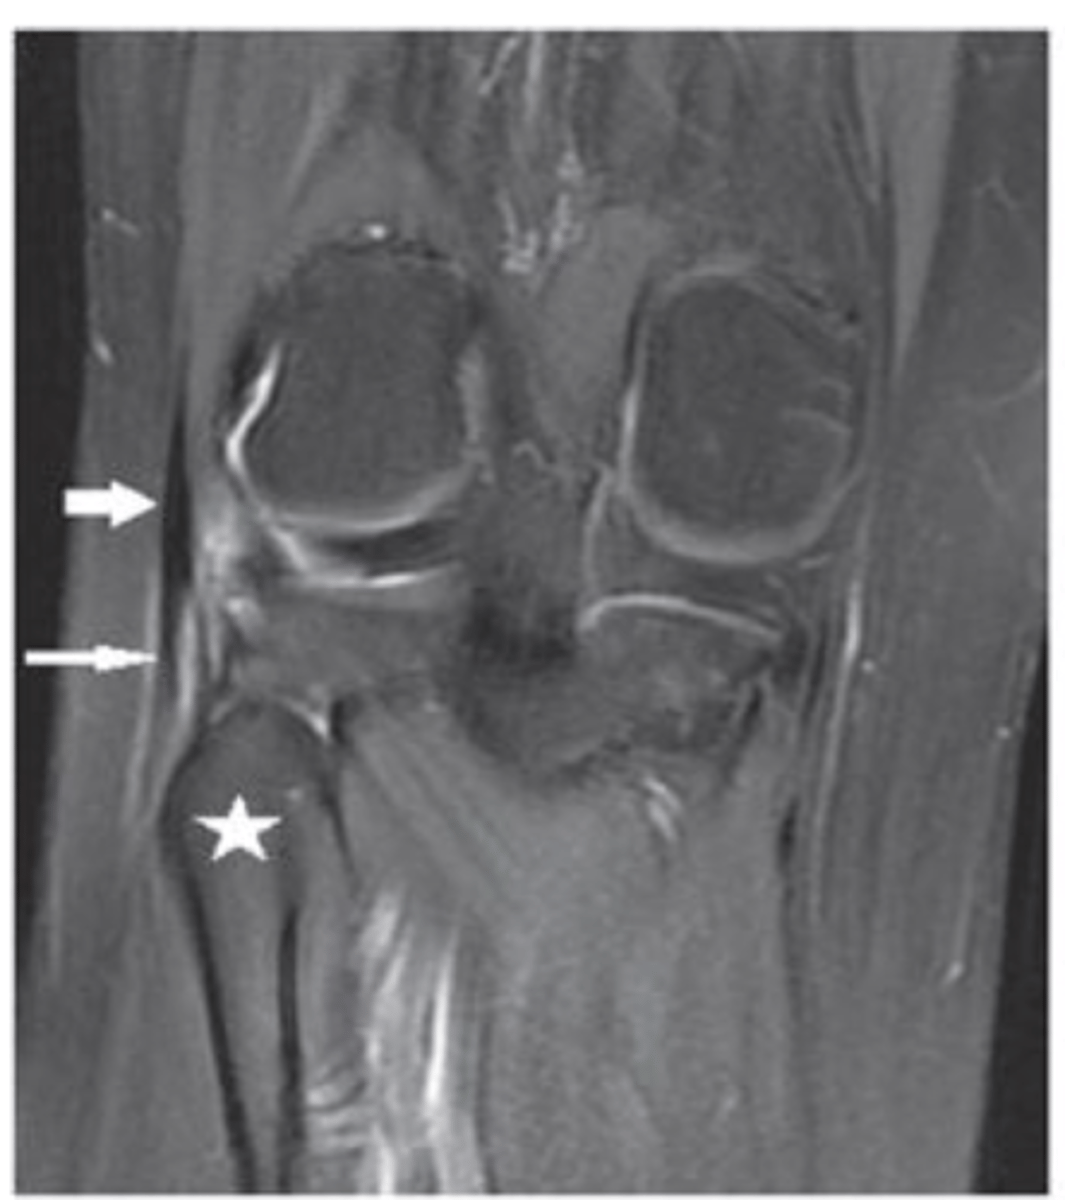

Grade III MCL tear

Define the pathology.